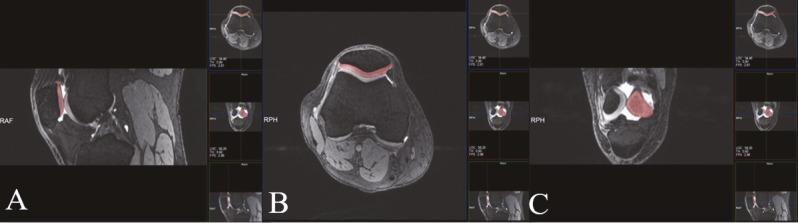

A total of203 patients with different degree of patellar chondromalacia (103 male, 100 female) and 52 control subjects (19 male, 33 female) were included and grouped according to sex, age, body surface area (BSA), body mass index (BMI) and patellar chondromalacia classification. All measurements were completed with 3T magnetic resonance imaging (MRI). Articular cartilage and IFP volume were measured in saggital plane using double echo steady state (DESS) and DIXON sequences, respectively. Patellar cartilage damage was graded using modified outerbridge classification, and the relations among cartilage volume and BMI, BSA, IFP, IMT were statistically assessed.

共纳入 203 例不同程度髌股软骨软化症患者(男 103 例,女 100 例)和 52 例对照组(男 19 例,女 33 例),根据性别、年龄、体表面积(BSA)、体重指数(BMI)和髌股软骨软化症分类进行分组。所有测量均采用 3T 磁共振成像(MRI)完成。关节软骨和 IFP 体积分别采用双回波稳态(DESS)和 DIXON 序列在矢状面测量。髌股软骨损伤采用改良 outerbridge 分级进行分级,并对软骨体积与 BMI、BSA、IFP、IMT 的关系进行统计学评估。